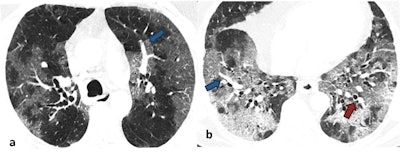

Ground-glass opacity (GGO) was the dominant abnormality found in all 51 cases. Pure GGO was observed in 15 (29%), GGO with crazy-paving pattern was seen in 15 (29%), and GGO mixed with consolidation was noted in 21(41%). Perilesional or intralesional segmental or subsegmental pulmonary vessel enlargement was observed in 36 (71%) of cases.

"Most of the findings we observed were in tune with the published data, however, low prevalence of chest CT findings in our population was intriguing," they reported. "Secondly, segmental pulmonary vessel enlargement was a unique finding in COVID-19 pneumonia that we observed in our cohort. This finding is peculiar to COVID-19 pneumonia and has a diagnostic value."

Looking to the future, the Srinagar team is now working on vascular complications in COVID-19 pneumonia. These are seen quite frequently in severe COVID-19 cases and contribute to mortality.

"We are trying to connect the three dots of imaging, histopathology, and clinical data to analyze the vascular complications of COVID-19," Wani and Parry elaborated. "We are trying to find out what additional therapeutic strategies need to be adopted to reduce the vascular complication related mortality in severe COVID-19. We are focusing on immunothrombosis as the underlying pathophysiological mechanism for high rates of vascular complications in COVID-19."